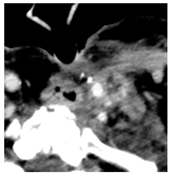

| 1 | 75–100 | 860 | ![]() Axial post-contrast fat-suppressed T1-weighted MRI shows a solidly enhancing left retroarticular tumor. | ![]() Axial CT image obtained 1 day after injection shows the NBTXR3 nanoparticles (arrows) in the tumor with leakage into the surrounding soft tissues. |